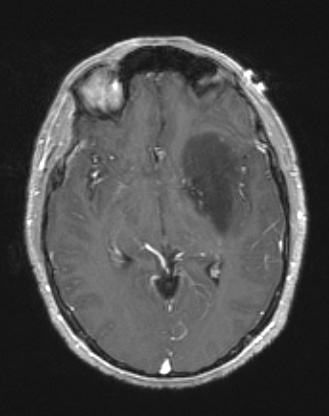

A T1-weighted image with administered contrast fails to show enhancement.